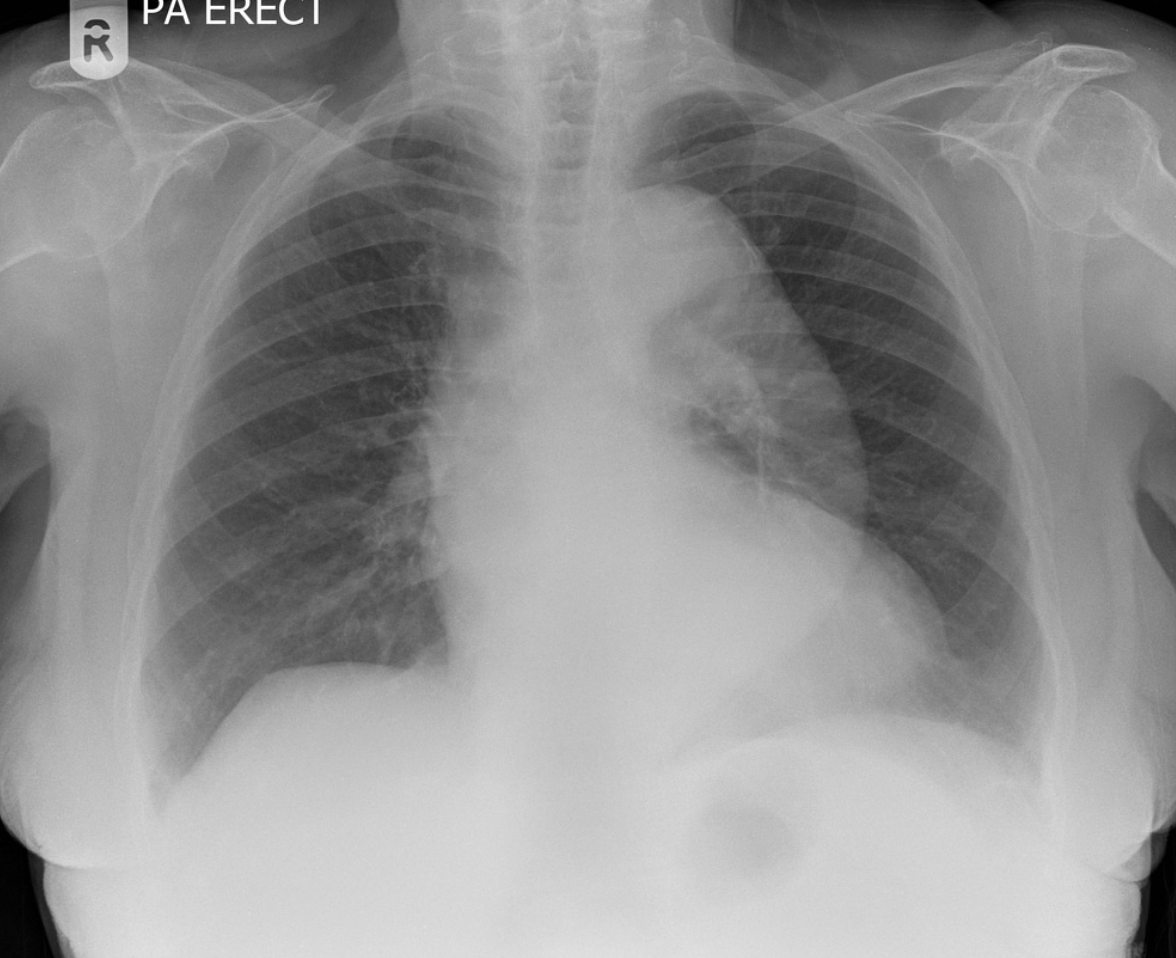

Scimitar syndrome (Anomalous right lower pulmonary vein draining into IVC)